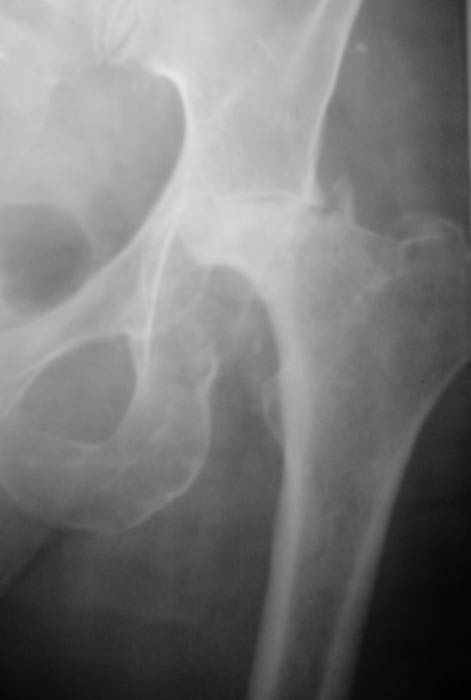

Уважаемые коллеги! Прошу Вас оказать консультативную помощь. Женщина, 44 года, инвалид 3 группыДиагноз: СКВ, асептический некроз головок обеих бедернных костей, двусторонний артроз 3-4 ст., болевой синдром, приводящая контрактураправого тазобедренного сустава, хронический волчаночный гепатит, спленомегалия, анемия, СКВ с 2002 года (подтверждена наличием lupus-клеток), получала специфическую терапию, медрол 16 мг/сут. Боли в левом тазобедренном суставе появились в сентябре 2003 года. Динамика отражена на рентгенограммах. В марте 2004 года - синдром Мэллори-Вейса, кровотечение остановлено эндоскопически. Объективно: кожа бледная, пастозность, отечность лица, высыпания на лице практически отсутствуют. Печень +6 см, селезенка не пальпируется. АД140/80, пульс 100, дыхание 15.

Ходит с тростью, хромота. Объем движений в суставах: справа - сгибание 90, разгибание 170, отведение 0, приведение 20, внутренняя ротация 15;слева - сгибание 90, разгибание 180, отведение 0, приведение 20, внутренняя ротация 0, наружная ротация 20. ЭКГ - отклонение ЭОС влево, гипертрофия левого желудочка, дистрофические изменения миокардаОбщий анализ крови: Э. 3,6, Hg 100, цп. 0,83, л.7,3, э.1, п.3, с.72, л.19, м.5, СОЭ 5 Общий анализ мочи: объем 120,0, уд.вес 1008, желтый, р-ция кислая, сахар/белок/цилиндры нет, эпителий и эритроциты единичные, Л.1-2, солиоксалатовые в небольшом к-ве. Биохимический анализ крови Билирубин 11,5 ммоль/л (прямой 0, непрямой 11,5), АСТ 0,24, АЛТ 0,61, протромбиновый индекс 100, рекальцификация 150, фибриноген 1,99,толерантность 8, фибринолитическая активность 240, общий белок 74,3, сиаловые кислоты 250 ед., С-реактивный белок 0. Пациентка желает выполнить тотальное эндопротезирование. Допустимо ли выполнение подобной операции? При каких условиях, дополнительной терапии? Особые предоперационные мероприятия? Личный опыт? Комментарии?Мнения? Заранее благодарю!!! С уважением, А.В.Владзимирский Донецкий НИИ травматологии и ортопедии

Уважаемый коллега,в практике нашего отделения эндопротезирования крупных суставов был похожий случай, у солдата 19 лет, вдруг ни с того, не с сяго, атрофировался правый глаз, и так - же, даже быстрее, рассосался левый тазобедренный сустав, долго умные люди думали и гадали, что это такое , вплоть до мифического рака глаза с метастазами. Пишу просто и с юмором, уж простите что нет заумных фраз. Лечился в 3 - х госпиталях, - долго думали заумно и интерестно, пока не взяли РНГА на Хлпмидии и соскоб из уретры, оказался реактивный ( да, вот такой быстрый и непонятный ) синдром Рейтера , рентгенологическая картина точно такая - же. Потом поступила женьщина 43 лет, картина аналогичная, только болезнь длилась 3 года. при РНГА тесте - хламидии. Уж не знаю, успел ли вам вовремя написать, пусть я и ошибаюсь, однако опыт не пропьешь, проверьте на всякий случай. В плане оперативного лечения, то уж простите, с вышеуказанными высказованиями категорически не согласен, протез только безцементный, желательно Споторно ( и ножка ляжет как надо, да и вертлуга цела ) . С искренним Уважением. Н.С.